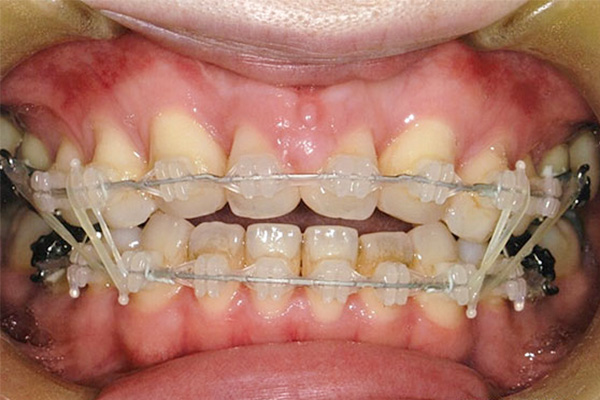

治療前